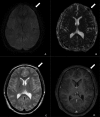

This is a case of a 22-year-old, HIV-negative, male patient with asymptomatic syphilitic osteomyelitis of the skull in the context of secondary syphilis. The diagnosis was made based on serology as well as CT and MRI scans. CT volumetric data was post-processed with cinematic rendering, which is a novel algorithm that allows for a photorealistic visualization of the lesions. Imaging and follow-up scans after treatment confirmed the diagnosis without the need to perform invasive procedures such as a biopsy.